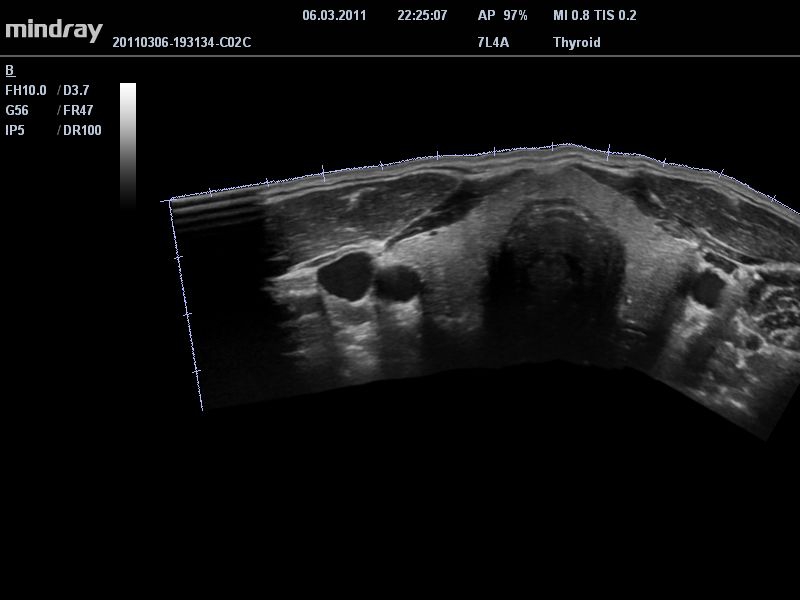

• Линейный ультразвуковой датчик Mindray 7L4A

• Технология PSH™: Гармоническая визуализация с фазовым сдвигом для улучшения контрастного разрешения и получения четкого изображения с меньшим уровнем шума.

• Технология iBeam™: Использование нескольких углов сканирования для формирования единого изображения, повышающего контрастное разрешение и качество визуализации.